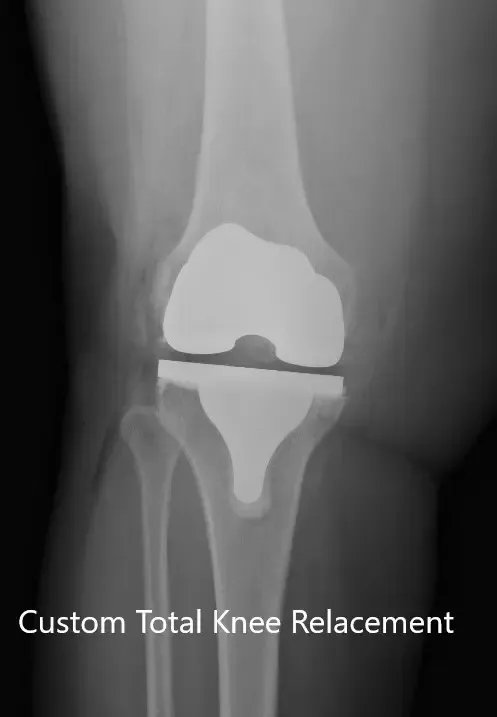

Los estudios de imagen revelaron osteoartritis tricompartmental severa de la rodilla derecha. Teniendo en cuenta el estilo de vida del paciente que limita el dolor de rodilla, se le recomendó un reemplazo total personalizado. Se discutieron riesgos, beneficios y alternativas con el paciente. Aceptó seguir adelante con la cirugía.

Como parte de la evaluación y planificación, se realizó una tomografía computarizada preoperatoria de las extremidades inferiores unas semanas antes de la cirugía. Se obtuvieron imágenes detalladas para una evaluación precisa de la anatomía y biomecánica del paciente. Se utilizaron datos completos para construir implantes e instrumentos personalizados y únicos para cada paciente.

IMPLANTES UTILIZADOS: Implante femoral personalizado con inserto de polietileno de 6 mm con una bandeja tibial personalizada y rótula de 32 mm.

Radiografía postoperatoria de la rodilla derecha que muestra visión AP y lateral.